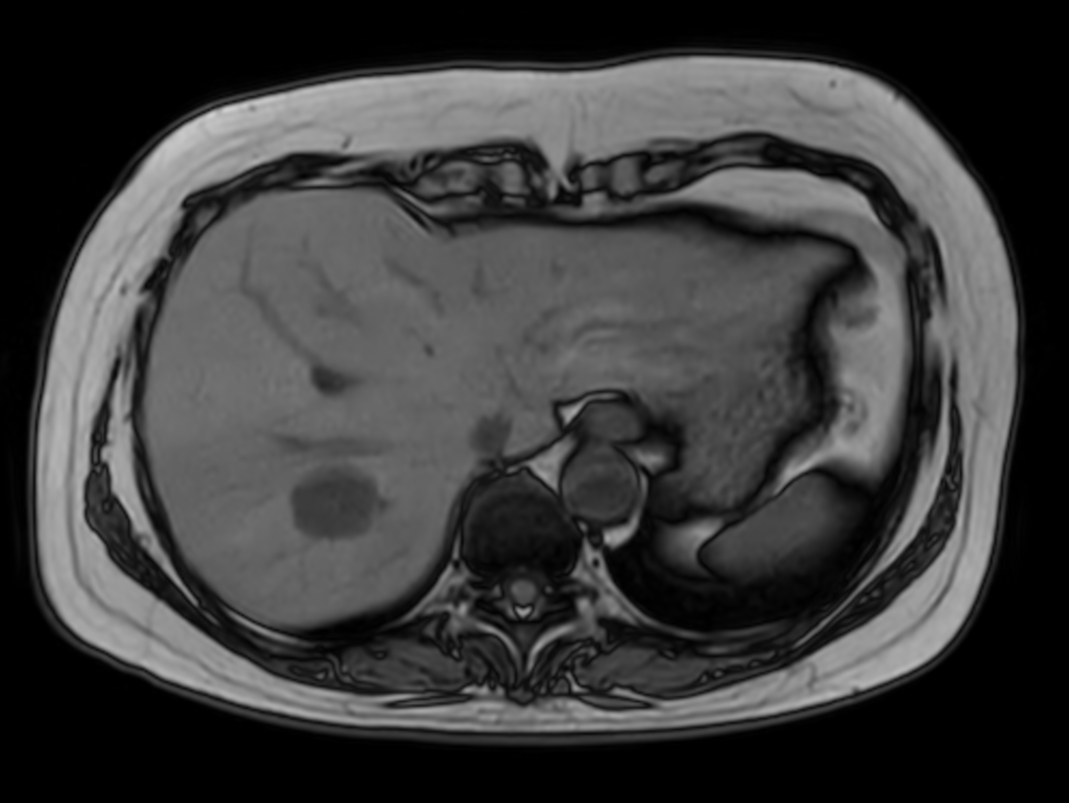

Axial T2w TSE

Axial T2w TSE (heavy)